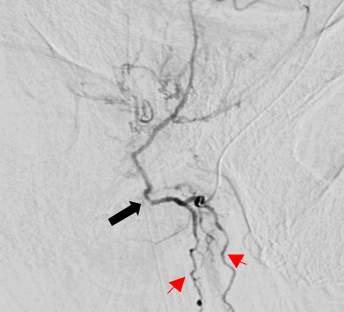

12306 Prostatic ar ter y embolization for intractable hematuria in patients with unregulated coagulation parameters: Three case repor ts Manuel Belmonte, Abdulghani Khogeer, Ghizlane Moussaoui, Rafael Melo, Louis-Martin Boucher, Tatiana Villalpando-Cabrera, Serge Carrier, Mélanie Aubé-Peterkin